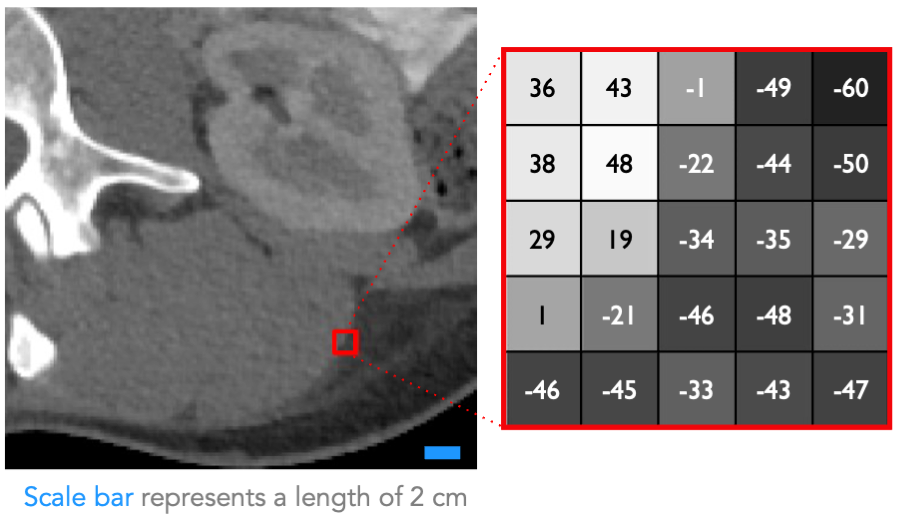

Subsection of an abodminal CT scan with a red square over an edge of an organ expanded out to a matrix to show the numerical values in that part of the image.

Section of abdominal computed tomography (CT) scan with a matrix of Hounsfield units (HU). (Source: Caryn Geady)